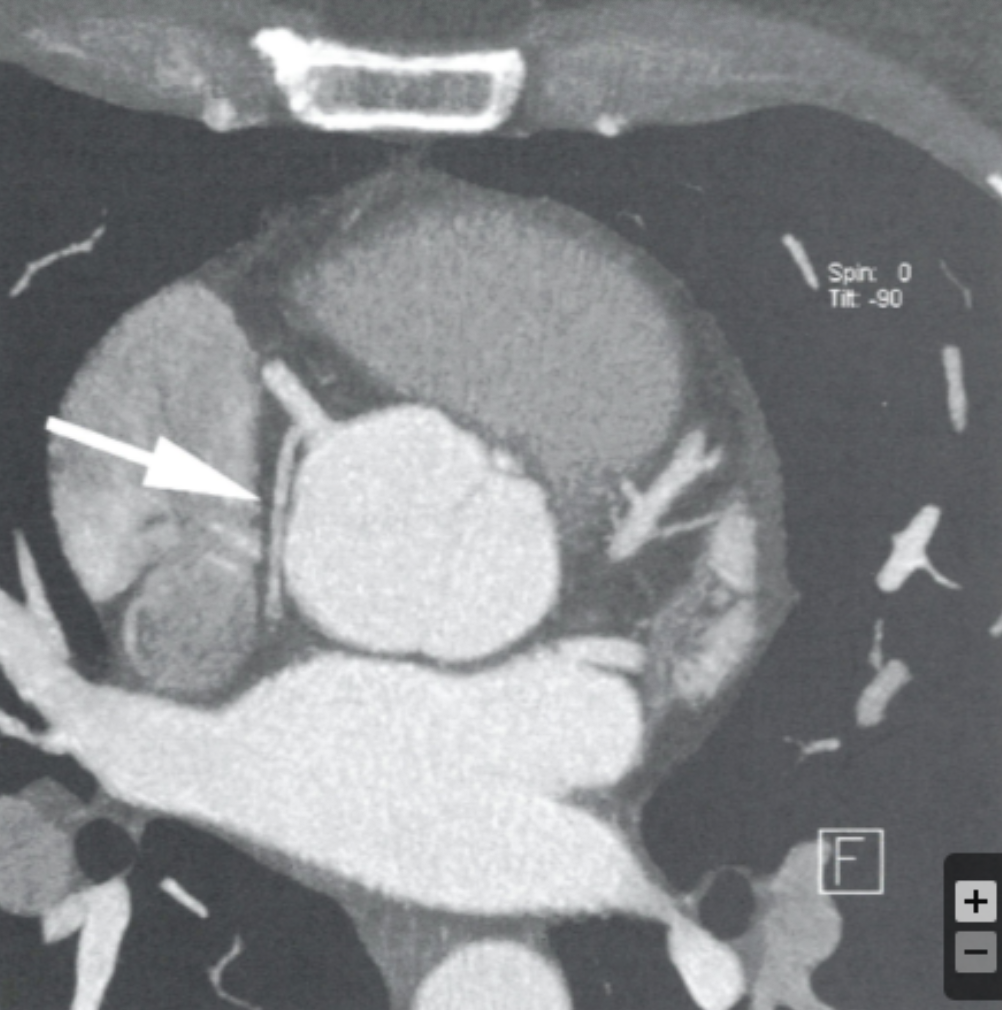

Describe the view and findings:

Describe the RCA findings in this image:

Cardiac Motion Artifact